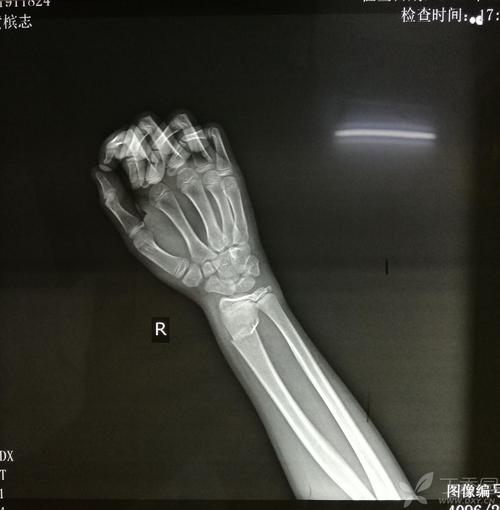

手桡骨远端骨折夹板,桡骨远端骨折夹板固定

桡骨远端骨折手法复位及小夹板固定外观

桡骨远端骨骺骨折手法夹板

对于无移位,稳定或通过复位可维持稳定的桡骨远端骨折首选石膏或夹板

儿童桡骨远端骨折手法复位杉树皮小夹板外固定治疗

左右桡尺骨远端骨折,手法夹板固定 [病例帖]

桡骨远端骨折夹板固定

右桡骨远端骨折

右手桡骨远端骨折图片

桡骨远端骨折图片

右桡骨远端骨折图片

桡骨远端骨折固定图片

正常桡骨远端骨折图片

桡骨远端骨折复位图片